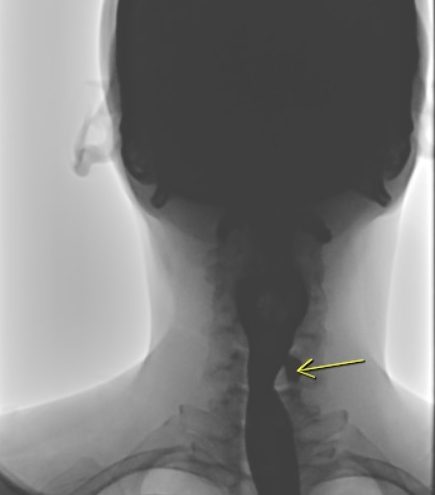

Many medical and surgical disciplines deal with KJD because of the wide range of symptoms and presentations. These include radiology, otolaryngology, gastrointestinal, and endocrinology. As a consequence of this, several forms of diagnostic imaging, such as CT scans, esophagoscopes, barium esophagram, and ultrasound, are utilized in the process of determining whether or not KJD is present.

Frequently, a barium esophagram is performed to diagnose a pharyngeal diverticulum. However, occasionally it could be challenging to differentiate ZD from KJD using only a barium esophagram, particularly if the diverticula are big. Therefore, another diagnostic technique such as a CT scan can be utilized to determine the diverticulum’s anatomical origin and to arrange the proper surgery.